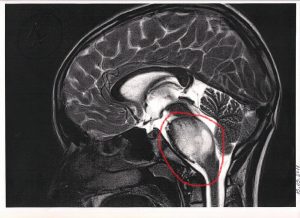

Na zdjęciach widać to tak : ten z lewej najjaśniej świecący- to potwór z 25.05.2018 i takiego go zobaczyliśmy po raz pierwszy. Po naświetlaniach w zasadzie całkiem zniknął, ateraz wyłania się powoli z cienia jak zły duch…

The photos shows: the first photo is from w got the diagnosis, the bright region is the moster we are fighting with since may last year…it almost dessapeared after radiotherapy and now is emerging from the shadows again…